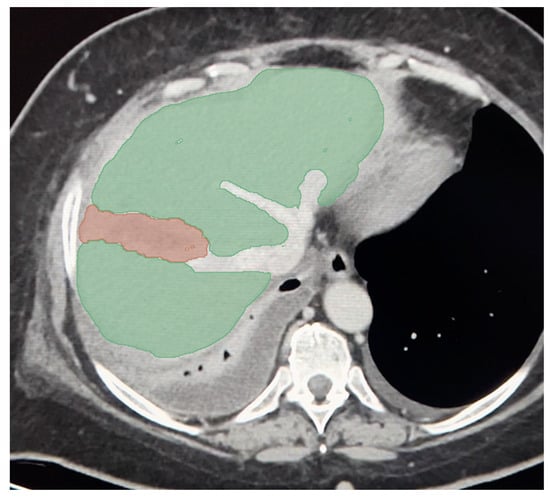

- Dreizin, D.; Chen, T.; Liang, Y.; Zhou, Y.; Paes, F.; Wang, Y.; Yuille, A.L.; Roth, P.; Champ, K.; Li, G.; et al. Added value of deep learning-based liver parenchymal CT volumetry for predicting major arterial injury after blunt hepatic trauma: A decision tree analysis. Abdom. Radiol. 2021, 46, 2556–2566. [Google Scholar] [CrossRef] [PubMed]